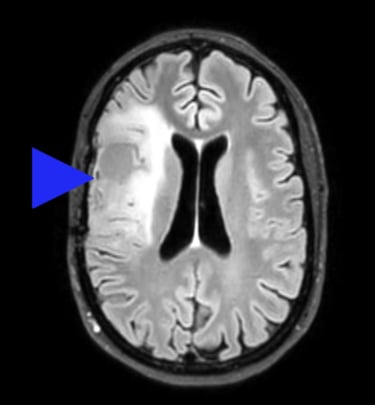

Ceci n'est pas une image tirée d'internet, mais bien mon propre cerveau. Tous droits réservés.

Parce qu'à présent je me souviens: depuis presque un an, j'ai, chaque matin, une sensation étrange, indescriptible dans la main qui dure 30 secondes puis s'en va. Je ne m'étais pas inquiétée, mais à présent je fais le lien. C'est sûrement de l'épilepsie. Il semble que des gens fassent une crise d'épilepsie et puis plus rien d'autre. J'espère que c'est ça et j'apprends que la NHS (Service de Santé au Royaume Uni) m'a retiré de la liste d'attente pour mon rendez-vous chez le neurologue. Mais 6 semaines plus tard, une deuxième crise. Là, la NHS ne rigole plus, j'ai un rendez-vous rapidement, puis un IRM. Ensuite plus de nouvelles, jusqu'à ce que le neurologue m'appelle tout en panique, me dit assis à une table de café que mon dossier était par erreur au fond d'une pile de résultats négatifs. Mais j'ai une "lésion" au cerveau. Encore un peu de temps pour un rendez-vous chez un neurochirurgien. Il m'annonce avec une froideur factuelle que j'ai une tumeur au cerveau, qu'il faut m'opérer, peut-être radio et chimiothérapie. Effondrée, terrifiée, je prends refuge pour l'après midi chez mon ami Stuart, pleurant au son du violon de ses élèves, avant de rentrer chez moi.

Après quelques mois, on m'enlève un morceau de cerveau. Contre toute attente c'est une bonne chose. Les maux de têtes atroces dont je souffrais depuis des années disparaissent brusquement. Ma chirurgienne n'est pas étonnée: mon cerveau était tellement sous pression qu'il aurait voulu sortir de sa boîte! Elle n'a retiré que le bout malade, et je peux tout faire comme avant. De plus, la tumeur est mise dans la case "croissance lente" et donc ni radio ni chimio pour l'instant.